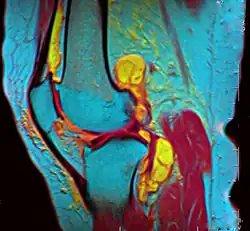

A grayscale MRI of a knee – different gray levels indicate different tissue types, requiring a trained eye.

A pseudocolor MRI of a knee created using three different grayscale scans – tissue types are easier to discern through pseudo color.